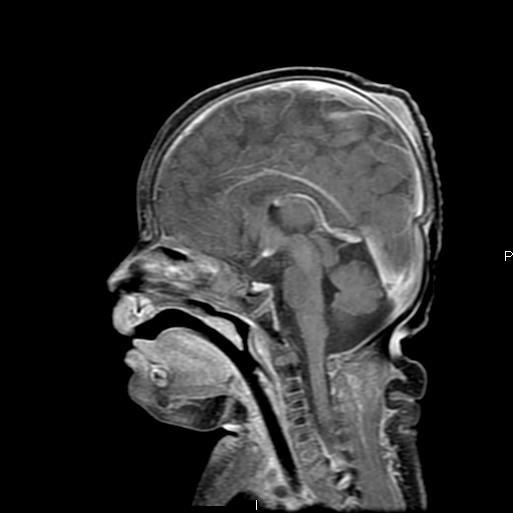

Sweep the Midline: What parts are missing?

Run the Rim…where is the cortex “too thick?”

“Missing”=disorganized rostrum, genu, anterior body of the corpus callosum Cortex of the anterior medial frontal lobes “too thick” with fused grey matter across the anterior midline where the “genu” should be.